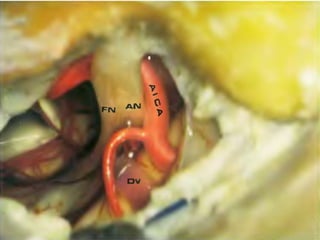

Different positions of the anterior inferior cerebellar artery (AICA) in relation to the

Fig. 74a, b The reference level is the acousticofacial nerve

bundle. The anterior inferior cerebellar artery, lying between

the auditory and facial nerves, is found in 38% of cases.